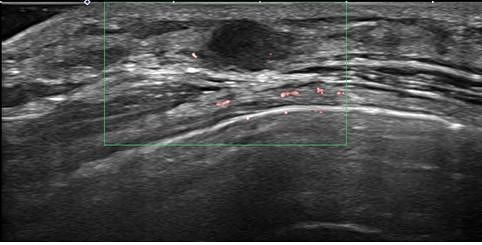

조기 유방암 환자의 초음파 검사 사진